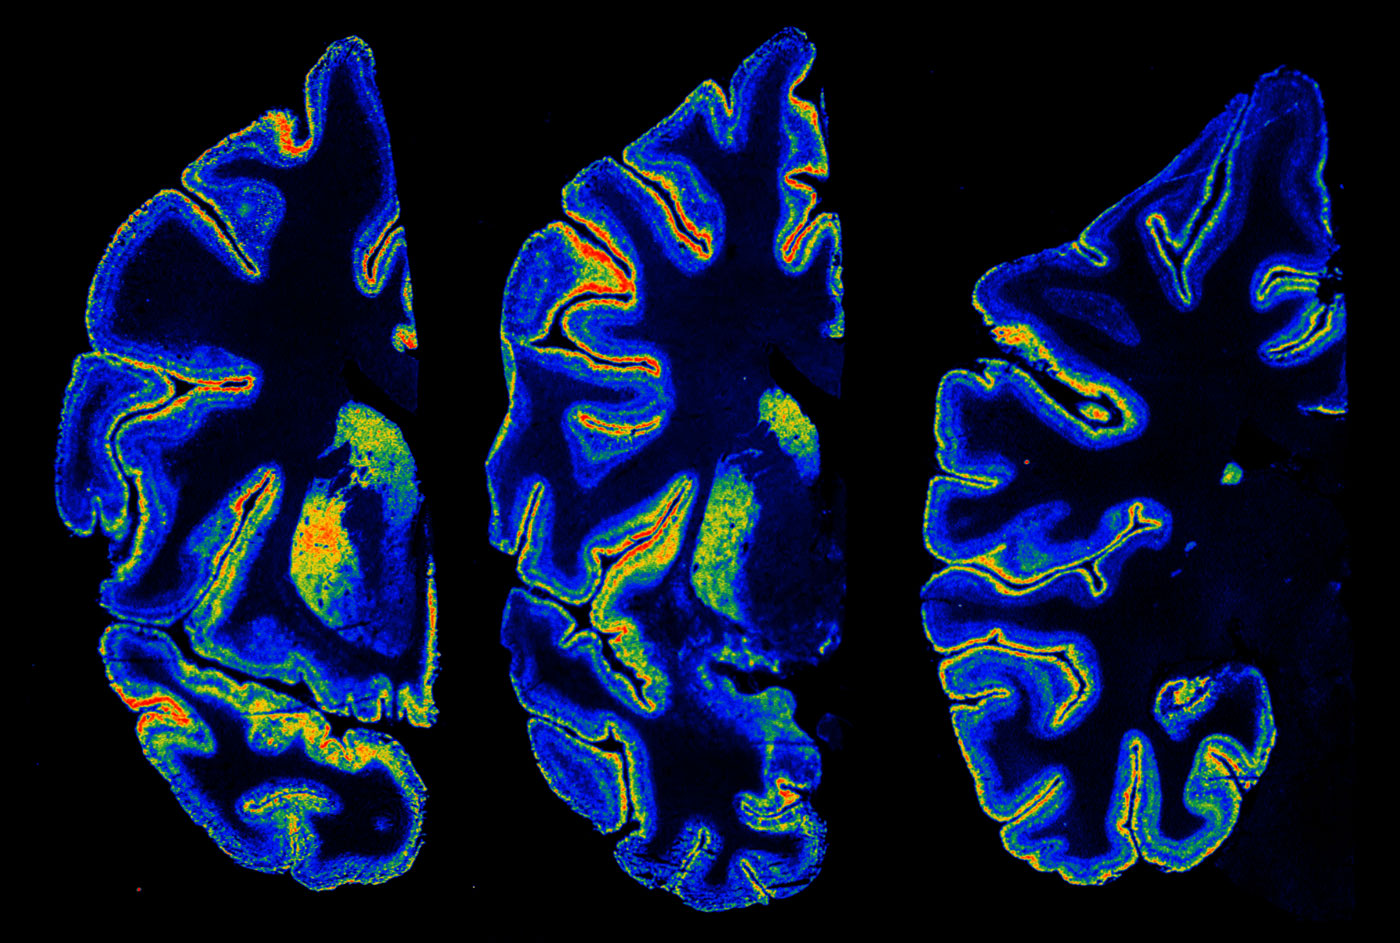

Researchers looked at young people who used cannabis regularly and compared their brain activity to teens who did not use it. Instead of relying only on self-reported information, they used brain imaging to examine how different regions responded during tasks involving learning, planning, and emotional regulation. The goal was not to stigmatize young people but to understand whether marijuana use during adolescence could shape cognitive functioning later on. The study included participants from different backgrounds and focused on patterns that appeared consistently among frequent users. Scientists found changes in brain connectivity, especially in areas involved in memory and problem-solving. These differences did not necessarily mean permanent damage, but they suggested that early exposure may alter the pace or direction of brain development.

One of the clearest findings involved the hippocampus, a region closely tied to memory formation. Teens who used cannabis regularly showed reduced activity when performing memory-based tasks. Researchers explained that this could affect how easily young people store and recall new information. In a school setting, this may mean that studying, focusing, and keeping track of assignments becomes more challenging. Another area affected was the prefrontal cortex, which helps with decision-making and controlling impulses. The research team noted that these changes do not make teens incapable of good judgment, but they may increase the difficulty of evaluating risks or resisting peer pressure.